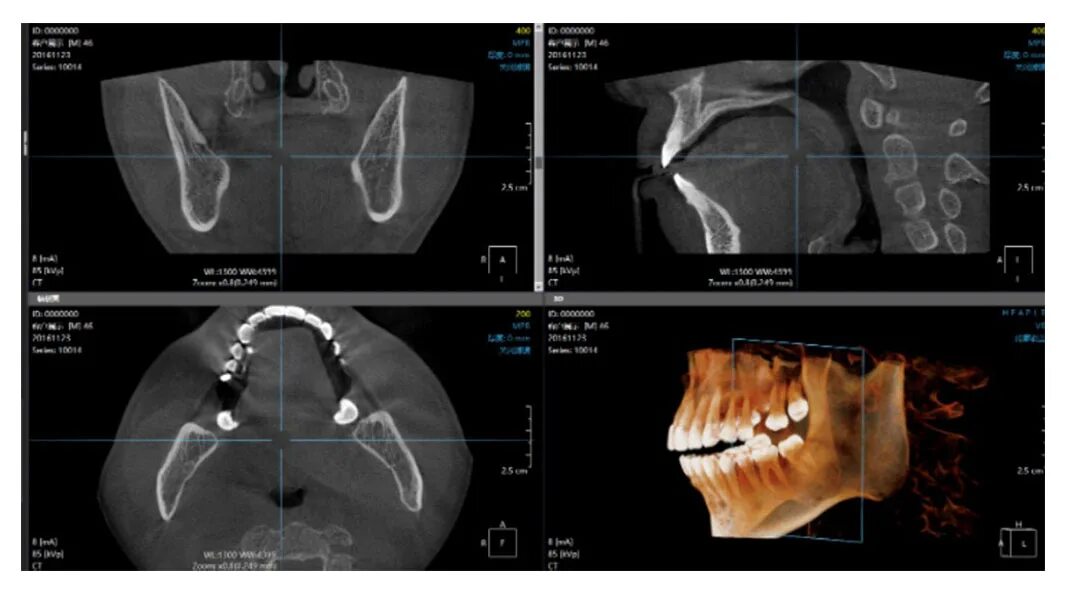

Какой программой открыть кт